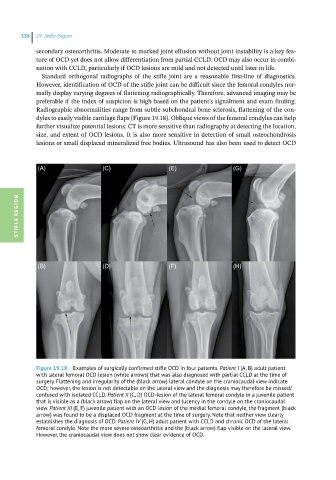

Figure 19.18 Examples of surgically confirmed stifle OCD in four patients. Patient I (A, B) adult patient

with lateral femoral OCD lesion (white arrows) that was also diagnosed with partial CCLD at the time of

surgery. Flattening and irregularity of the (black arrow) lateral condyle on the craniocaudal view indicate

OCD; however, the lesion is not detectable on the lateral view and the diagnosis may therefore be missed/

confused with isolated CCLD. Patient II (C, D) OCD-lesion of the lateral femoral condyle in a juvenile patient

that is visible as a (black arrow) flap on the lateral view and lucency in the condyle on the craniocaudal

view. Patient III (E, F) juvenile patient with an OCD lesion of the medial femoral condyle, the fragment (black

arrow) was found to be a displaced OCD fragment at the time of surgery. Note that neither view clearly

establishes the diagnosis of OCD. Patient IV (G, H) adult patient with CCLD and chronic OCD of the lateral

femoral condyle. Note the more severe osteoarthritis and the (black arrow) flap visible on the lateral view.

However, the craniocaudal view does not show clear evidence of OCD.